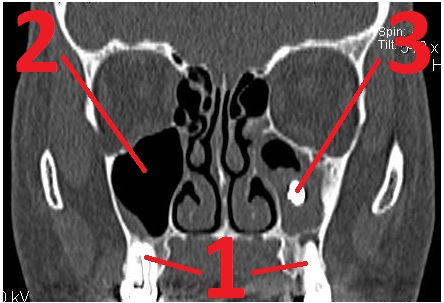

Кисты верхнечелюстных (гайморовых) пазух при болезнях корней зубов.

1 – корни зубов, 2 – кисты верхнечелюстных пазух, растут от корней зубов (кисты – округлые «пузыри», на снимке выглядят серыми).